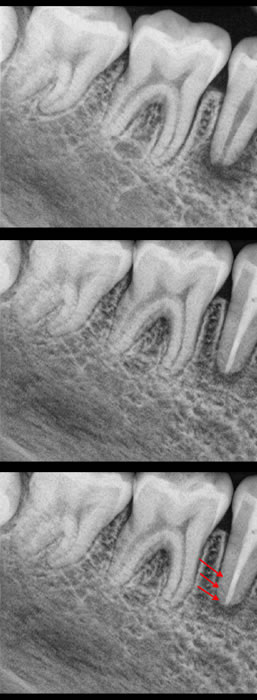

(see figures 10/11/12/13)

Figures 10,11,12,13: In these figures you can see the pre-op radiograph, the length confirmation used in this case is a gates gliddel because the apex is so large, the MTA fit in the apical 5mm, and the completed case with gutta percha over the MTA and a composite seal of the access point.